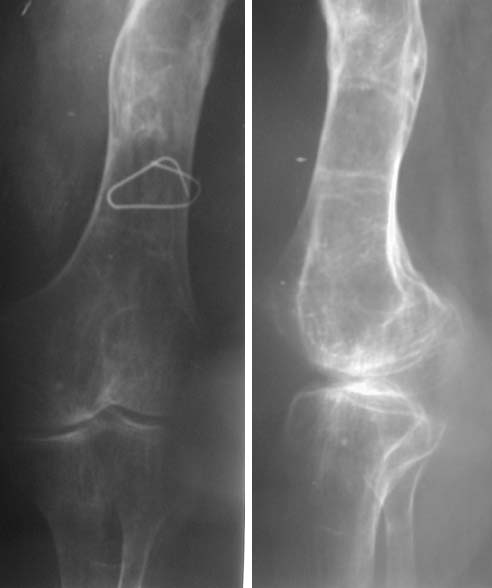

Необходимо сделать снимок на всю длину конечности и бедра для планирования операции. А также СТ для точного измерения анатомического укорочения, полагаю, что часть из 15 см. Будет исправлено при

устранении деформации.

Судя по представленному снимку, есть 3 деформации – Варусная в области ложного сустава - 70°, Вальгусная - 35° в средней трети бедра, и ещё одна вальгусная 8° в области дистального метаэпифиза бедренной кости. Если бы пациент попал ко мне, я сделал бы трилокальный остеосинтез – Открытый погружной копрессионный в области ложного сустава, остеотоми на вершине деформации средней трети бедра для удлинения и коррекции деформации и коррегирующую остеотомию через верхний край мыщелков бедренной кости. Для оппонентов такой тактики сразу оговорюсь, что коррекция анатомической и механической оси при наличии срастающегося ложного сустава критична для профилактики рефрактуры.